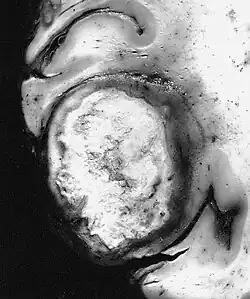

This figure illustrates how glioblastoma affects brain tissue.

Specialized cells in the central nervous system, such as glial cells, may proliferate abnormally and form gliomas.[6] Glioblastoma is an aggressive form of glioma.[7]